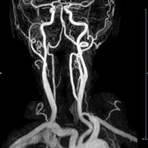

- MR-Angiografie ohne Kontrastmittel

- Time of Flight (TOF)-Angiographie

- Phasenkontrastangiographie (PCA). Geeignet zur Quantifizierung Stenose-/Insuffizienzgrad z.B. bei Herzklappen, falls echokardiographisch die Untersuchungsbedingungen eingeschränkt sind.

Je nach Fragestellung und Körperregion Gefäßdarstellung ohne Kontrastmittel bei Kontrastmittelunverträglichkeit oder terminaler Niereninsuffizienz möglich.